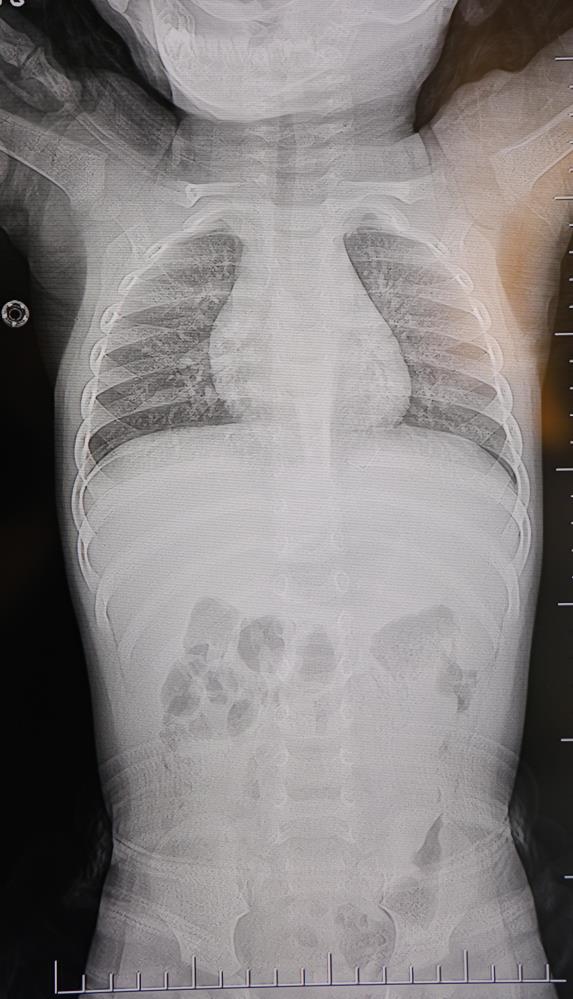

Baba Poyraz, bir gün acil serviste yapılan kontrollerde bebeğin belinde yabancı cisim olduğunu, çekilen filmlerde ise "L" şeklinde zımba teli tespit edildiğini söyledi. Çeşitli hastanelere yönlendirildiklerini anlatan baba, uzun süre müdahale edilmediğini, daha sonra özel bir hastanede yapılan operasyonla zımba telinin çıkarıldığını kaydetti.

Poyraz, bebeğin doğduktan sonra sarılık diyerek kuvöze alındığını belirterek, "Bir hafta orada yattı. Sonra çıkardılar, eve getirdik. Eve geldikten sonra gece gündüz ağlaması hiç durmadı. Tekrar hastaneye götürdüm. Kaşınıyordu, bir hafta banyo yaptıramadık. Sonra duş aldırdım, bağırması daha da arttı. Belini açtık, sırtına baktık, bir şey var mı diye kontrol ettik, görünürde yoktu. Hastaneye götürdük, şurup verdiler. Aylar geçti. Daha sonra acilde bir doktor çocuğumun belinde yabancı cisim olduğunu söyledi. 184'ü aradım, şikayette bulundum. Başhekim yardımcısının yönlendirmesiyle tomografi çekildi. O zaman belinde zımba teli olduğu netleşti. Başka bir hastaneye götürdük, 'riskli, 8 yaşına kadar alınamaz' dediler, geri gönderdiler. Eve geldikten üç gün sonra oğlum bayıldı. Kardeşimle özel hastaneye götürdük. Orada filmlere baktılar, 'akciğere doğru gidiyor, L şeklinde zımba teli var, alınması lazım' dediler" dedi.